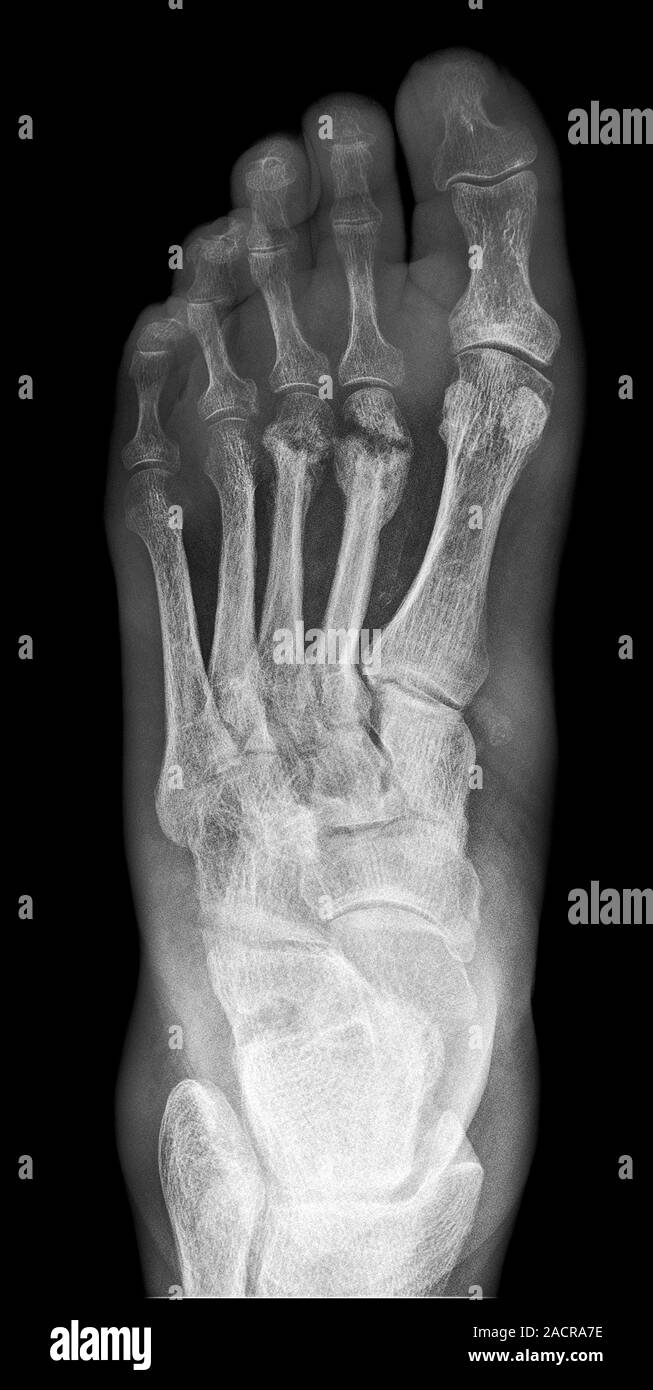

Infección en el hueso. Radiografía del pie de un paciente diabético

Xray mostrando la osteomielitis en el pie en una mujer diabética Pie Diabetico Osteomielitis Diabetic foot infections (dfis) typically begin in a. La amputación del pie o de la pierna se produce fundamentalmente por eventos relacionados con la isquemia o la infección, siendo esta última la causa principal 4. En la presente revisión se. Destruction of the base of 5th. La consecuencia más grave es la amputación 1. Diabetic foot osteomyelitis (dfo) is the. Pie Diabetico Osteomielitis.

Infección en el hueso. Radiografía del pie de un paciente diabético Pie Diabetico Osteomielitis Diabetic foot infections (dfis) typically begin in a. La consecuencia más grave es la amputación 1. Foot infections are a common and serious problem in persons with diabetes. Destruction of the base of 5th. La amputación del pie o de la pierna se produce fundamentalmente por eventos relacionados con la isquemia o la infección, siendo esta última la causa principal. Pie Diabetico Osteomielitis.